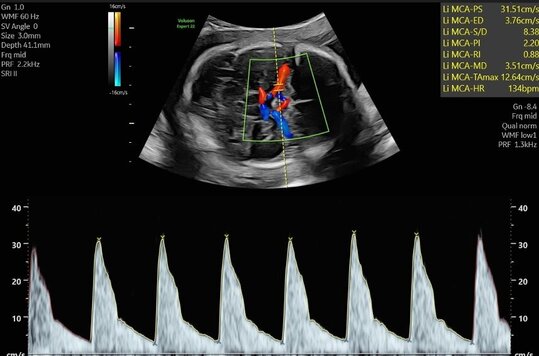

Ultraschalluntersuchung der mütterlichen und kindlichen Durchblutung (Farb-Dopplersonografie)

Die Durchblutung der Nabelschnur, der kindlichen Gefäße und des Mutterkuchens wird mittels einer speziellen Ultraschalltechnik durchgeführt. Mit der sogenannten (Farb-)Dopplersonografie können wir in der Pränataldiagnostik und Schwangerenambulanz die Versorgungslage überprüfen.

Auffällige Blutflussmuster können auf eine Mangelversorgung des Ungeborenen oder Auffälligkeiten im Kreislauf der Mutter hinweisen. Zu nennen wäre hier das erhöhte Risiko für einen schwangerschaftsbedingten Bluthochdruck. Mittels der Untersuchung können solche Probleme rechtzeitig erkannt und die Patientin entsprechend am UKS überwacht werden.

Nabelschnurarterie

Gehirndurchblutung (A. cerebri media)